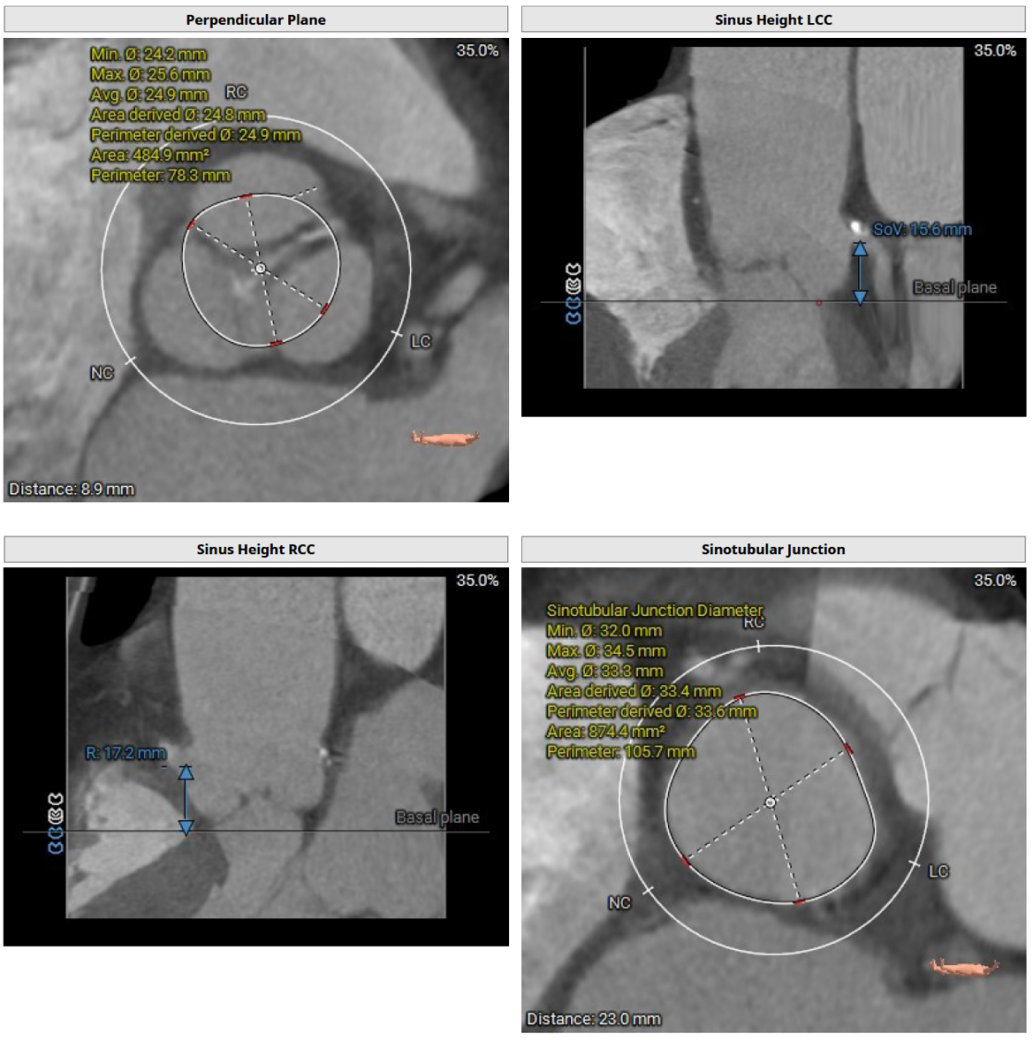

患者为三叶式主动脉瓣,重度反流。瓣叶交界轻度钙化。瓣环周长76.3 mm,平均径24.3 mm。LVOT周长77.3 mm,平均径24.0 mm。瓣上3.8 mm、5.0 mm、8.9 mm处空间为76.8 mm、82.8 mm、78.3 mm。STJ 周长105.7 mm,高度23 mm,升主周长126.5 mm 增宽、瓦氏窦大。综上所述建议TAV 27 瓣膜。左右冠高度15.6 mm、17.2 mm相对瓣膜支架可,冠脉风险低。股动脉入路血管轻度迂曲,双侧股动脉分叉高度可。腹主动脉、双侧髂总动脉散在钙化斑块。右侧股动脉平均内径最小6.3mm,左侧股动脉平均内径最小5.8mm,建议选择右侧股动脉为主入路。